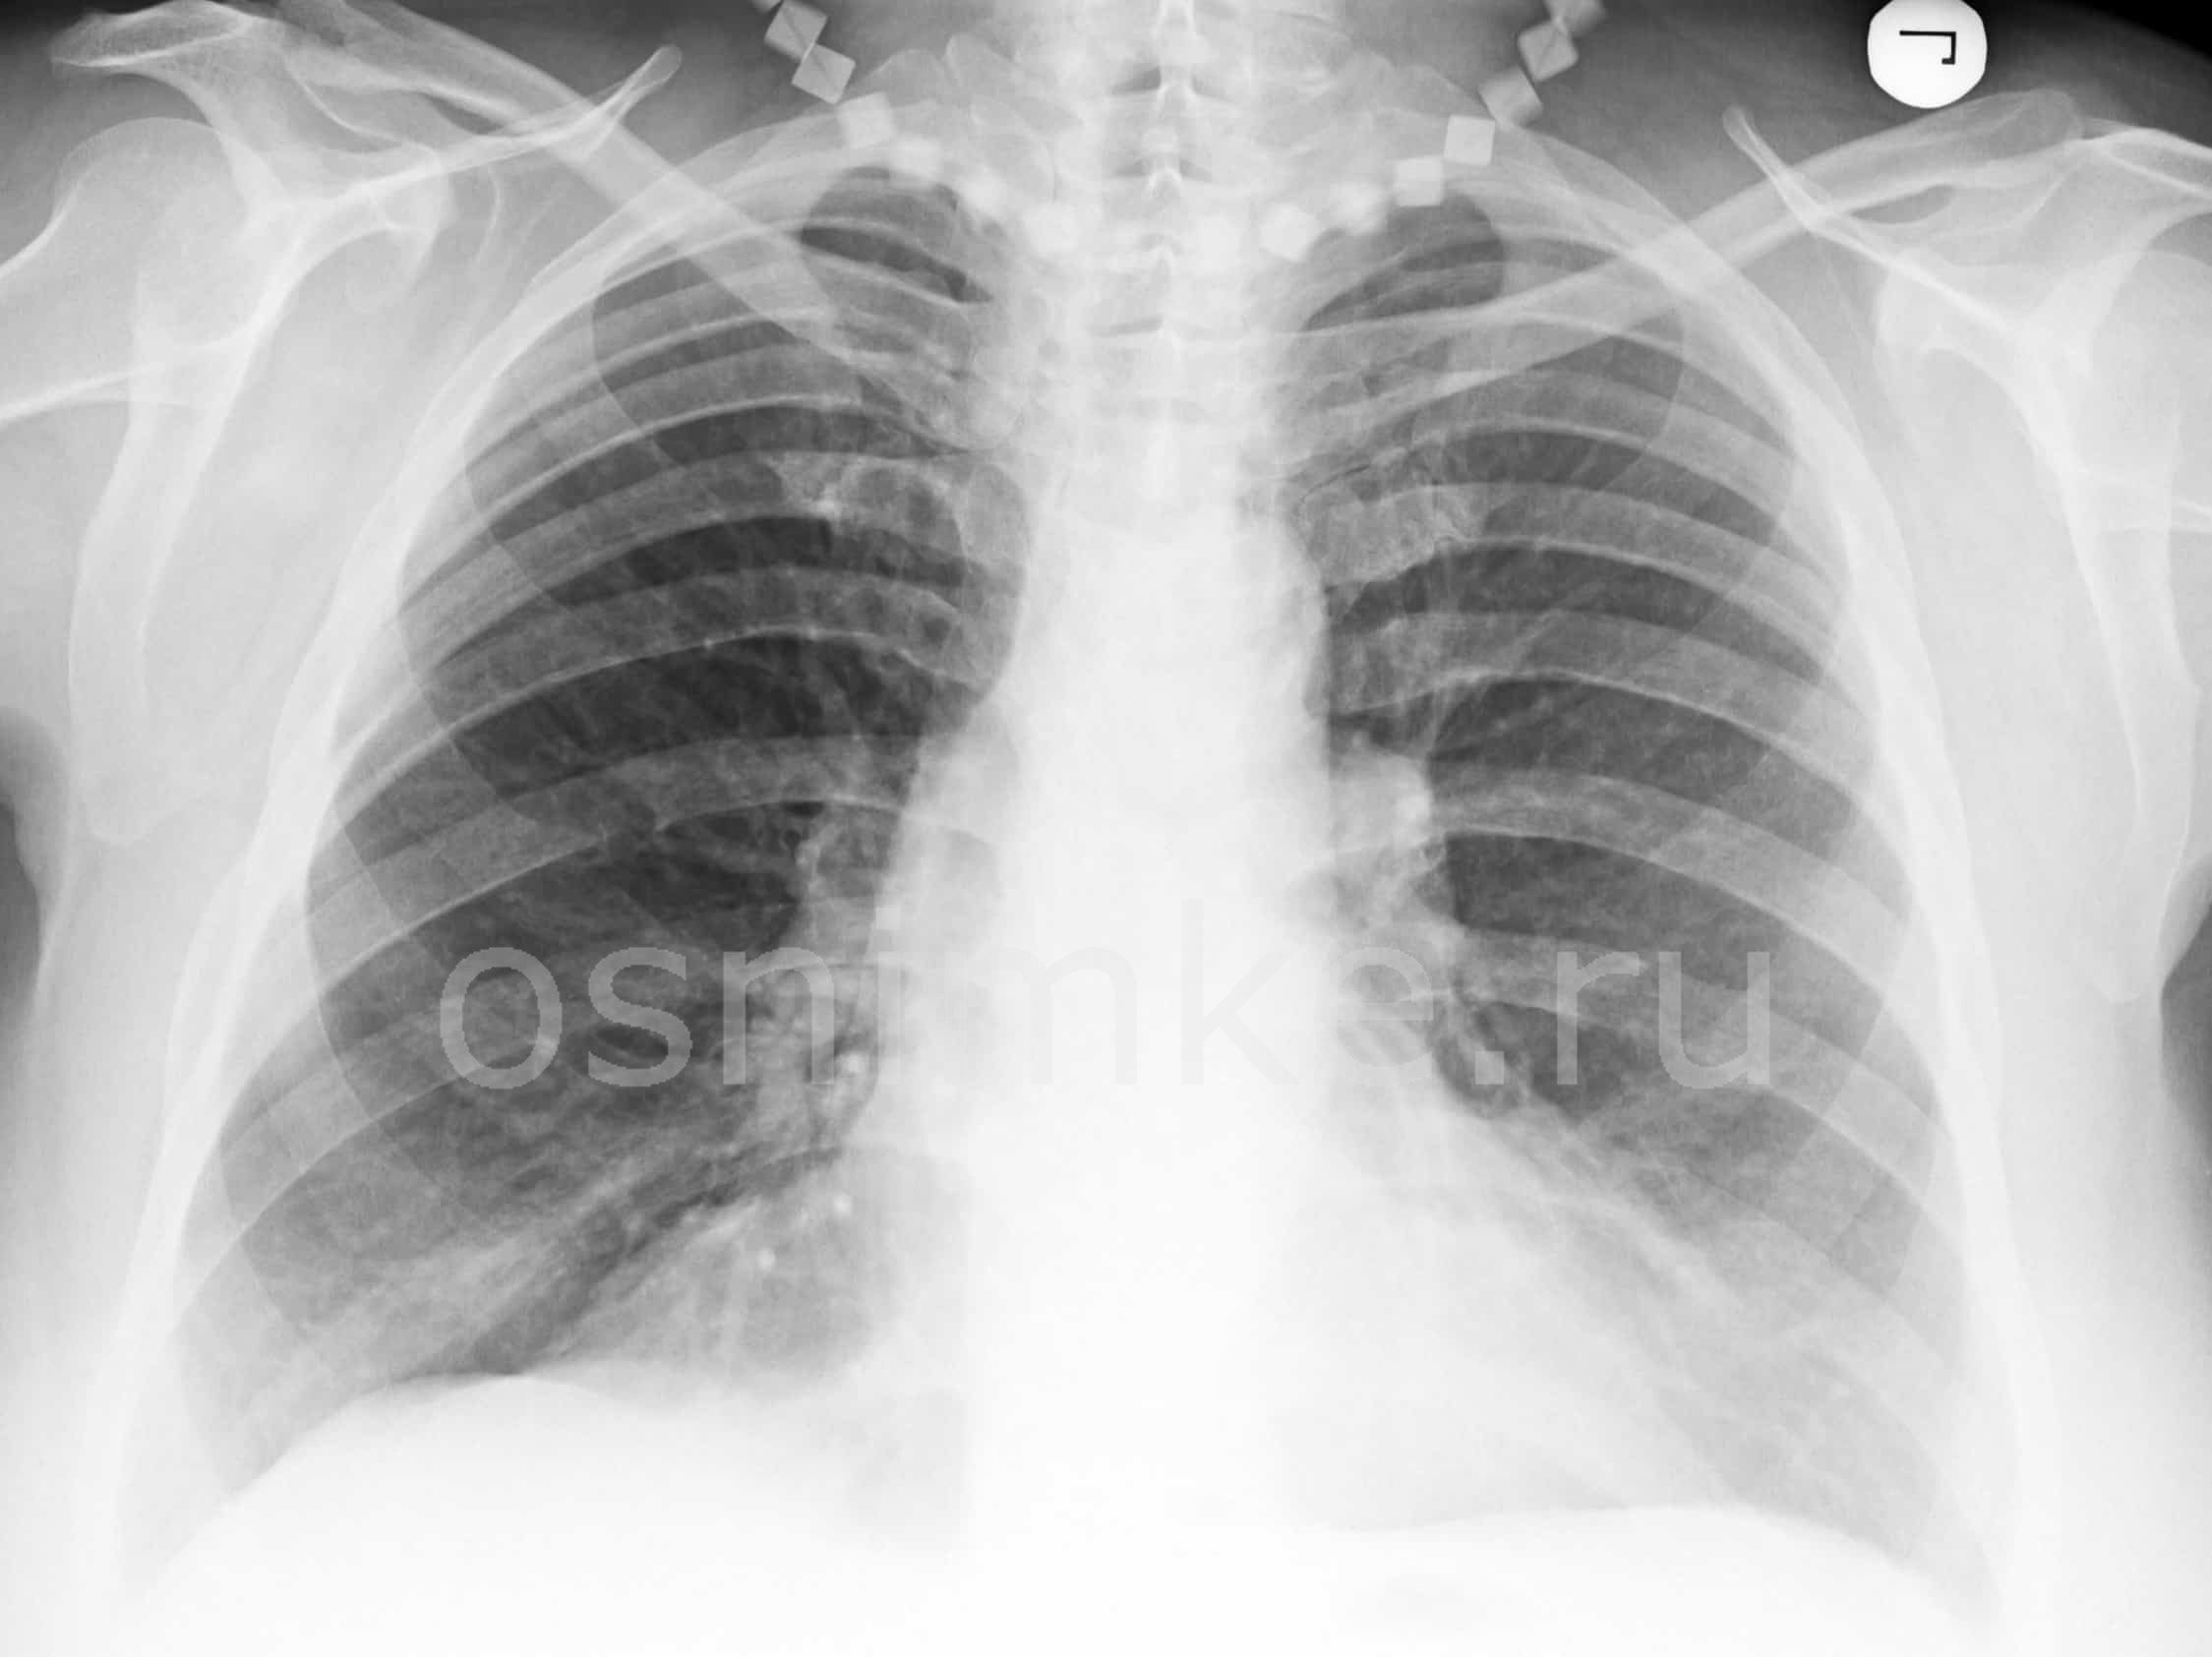

Как выглядит заболевание на рентгеновском снимке

Признаки воспаления лёгких на снимке называют «затемнениями», отображаются они белым цветом, поскольку само изображение является негативом.

Пятна и рентген-признаки:

- До 3 мм — мелкоочаговые.

- До 7 мм — среднеочаговые.

- До 12 мм — крупноочаговые.

- От 12 мм и более — фокусные.

Пневмония на снимке, в частности затемнения, характеризуются следующим образом:

- Распространённые. Визуализируют в пределах одного сегмента.

- Субтотальные. Затемнение большей части поля органа или нескольких сегментов.

- Тотальные. Патологический процесс охватывает всю область лёгочной ткани. Сильная пневмония слева

Важным этапом постановки диагноза остаётся отличие её от других заболеваний лёгких, коронавируса. Так, при бронхите будет отсутствовать затемнение на снимке, вместо этого — усиление лёгочного рисунка.

Усиление лёгочного рисунка

В случае присутствия инородного тела, наблюдается затемнение с чёткими краями, локализующееся в нижней доле лёгкого. Спутать с воспалением типичного характера сложно.

При плеврите, на снимке скопление экссудата в поражённой области. Плеврит выступает в качестве осложнения недолеченной пневмонии.

При пневмотораксе присутствует характерный уровень жидкости. На снимке отображается как просветление, лёгочный рисунок не просматривается.